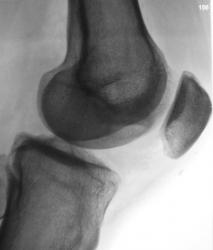

Пациент, врачом хирургом, направлен на рентгенографию коленного сустава в связи с болями. Пациент отмечает, что боли ощущает в течение уже 2-х лет. Ранее производилась рентгенография коленного сустава, однако патологических изменений выявлено не было.

А травмы не было? Латеральнее ММВ как будто бы фрагмент костной плотности. Может быть, болезнь Кёнига? С медиальной стороны щель сустава значительно уже, там же - участок разрежения в мыщелке бедра. На новообразование на первый взгляд не похоже. Без КТ мне трудно судить

Поддерживаю предподожение о б-ни Кенига. Хотя и отсутствует отслоившийся фрагмент, но тем не менее.

В протоколе написал - "состояние после перенесенной болезни Кенига". Хорошо дифференцируется "опустевшее ложе".